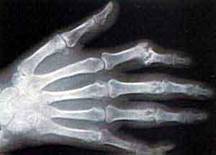

Skupmy teraz naszą uwagę nad dalszą prać Roentgena nad promieniowaniem X. Otóż Roentgen swoje odkrycie zademonstrował samemu ówczesnemu Cesarzowi Wilhelmowi II, który to słynął ze swojego zainteresowania nauką. Prezentacja odbyła się w Berlinie dnia 13 stycznia. Po spotkaniu z cesarzem 23 stycznia 1896 roku Roentgen wygłosił wykład o odkrytych przez siebie promieniach dla Fizycznego Towarzystwa Medycznego znajdującego się w Wurzburgu, czyli patrząc na datę w niecały miesiąc po ogłoszeniu swojego odkrycia. Co ciekawe, to patrząc z perspektywy czasu, był to praktycznie jedyny wykład jaki przeprowadził Roentgen dla tak dużego audytorium. W czasie tego wykładu Roentgen po prostu opisał w jaki sposób dokonał swojego odkrycia, oraz zademonstrował kilka uzyskanych przez siebie rentgenogramów. Naukowiec jednak wydawał się nie lubić publicznych wystąpień, jeszcze bardziej w czasie, gdy prowadził dalsze eksperymenty. Zrobił to tylko z powodu ogromnego zainteresowania opinii publicznej jego odkryciem. W czasie wykładu Roentgen dokonał prezentacji zastosowania swego odkrycia, a mianowicie dokonał prześwietlenia ręki anatomia von Kollikera, który znajdował się na sali. Sam von Kolliker był tak zachwycony otrzymanym zdjęciem, że zaproponował, aby odtąd odkryte promienie były nazywane promieniami Rentgena. Sugestia ta został przyjęta przez całe audytorium z wielkim entuzjazmem.

W pierwszych latach rozwoju diagnostyki promieniami X, lekarze zatrudniali fizyków, którzy wykonywali dla nich określone radiogramy. Dlatego też wielu fizyków założyło do tego celu własne laboratoria. W Wielkiej Brytanii pierwsze takie laboratorium powstało w marcu 1896 roku i zostało założone przez Cmpbella Swintona. Jednym z pierwszych pacjentów jaki zgłosił się do Swintona był mężczyzna, w którego głowie utkwiła kula. Oczywiście Swinton pomyślnie zlokalizował położenie kuli, jednak gdy mężczyzna zauważył że po badaniach zaczęły mu wypadać włosy z głowy, natychmiast zagroził że zaskarży do sądu Swintona. Jednak wszystko się szczęśliwie skończyło, bowiem kula z głowy pacjenta została usunięta, a włosy odrosły. To z kolei nasunęło pewien pomysł autorom czasopisma "Elektryczny Świat", którzy w czerwcu 1896 roku opublikowali artykuł w którym sugerowali, że promienie X, mogą być bardzo pomocne przy goleniu się. W tamtych czasach jeszcze nie zdawano sobie z tego sprawy, że użytkowanie promieni X, może stanowić zagrożenie dla zdrowia. Swinton stał się w niedługim czasie sławny, a jego laboratorium odwiedził nawet ówczesny premier Lord Salisbury. Naukowiec wykonał dla niego zdjęcie rentgenowskie jego ręki, które tak mu się spodobało, że natychmiast napisał list do Lady Salisbury. Żona premiera tak się zachwyciła dokonaniem Swintona, że sama zapragnęła posiadać podobne zdjęcia. Oczywiście Swinton spełnił jej prośbę.